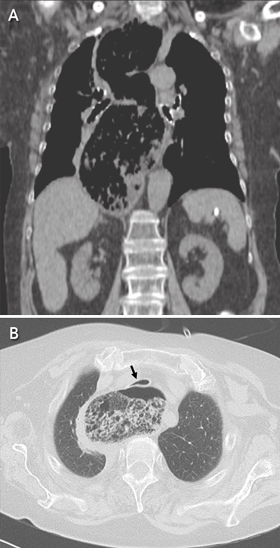

A chest computed tomography scan showed a severely dilated and tortuous oesophagus with retained food (Figure, A) causing compression of the trachea (Figure, B). The woman was successfully treated with laparoscopic Heller myotomy and discharged.